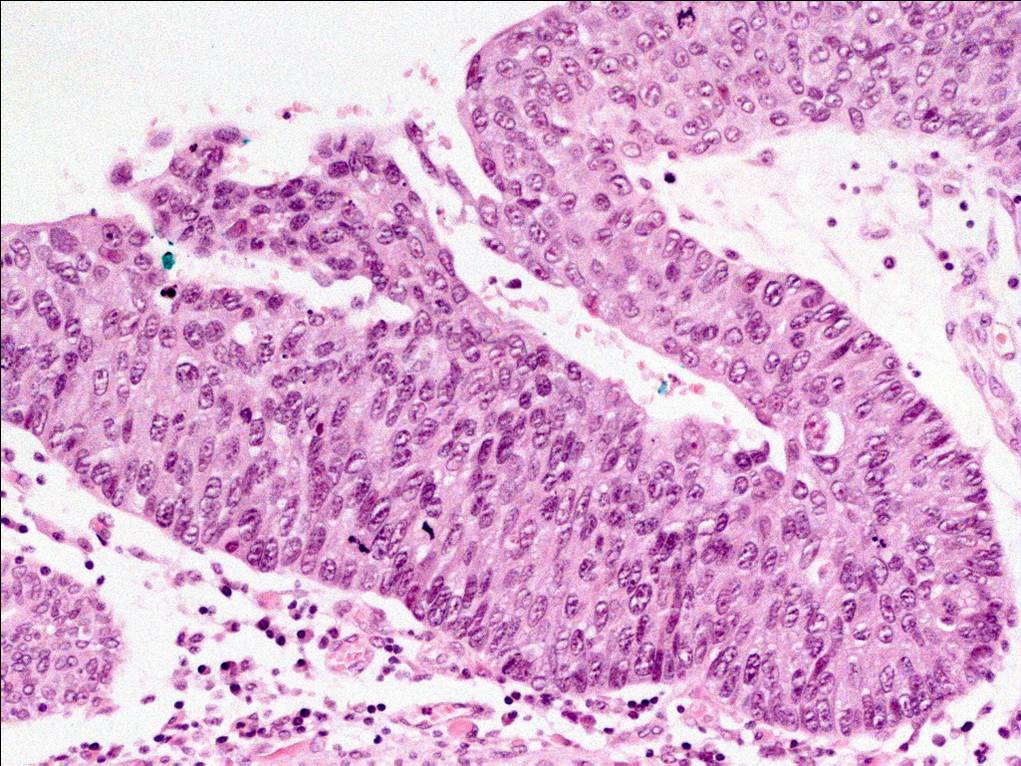

Bladder Flat Lesions

Case ID: 164